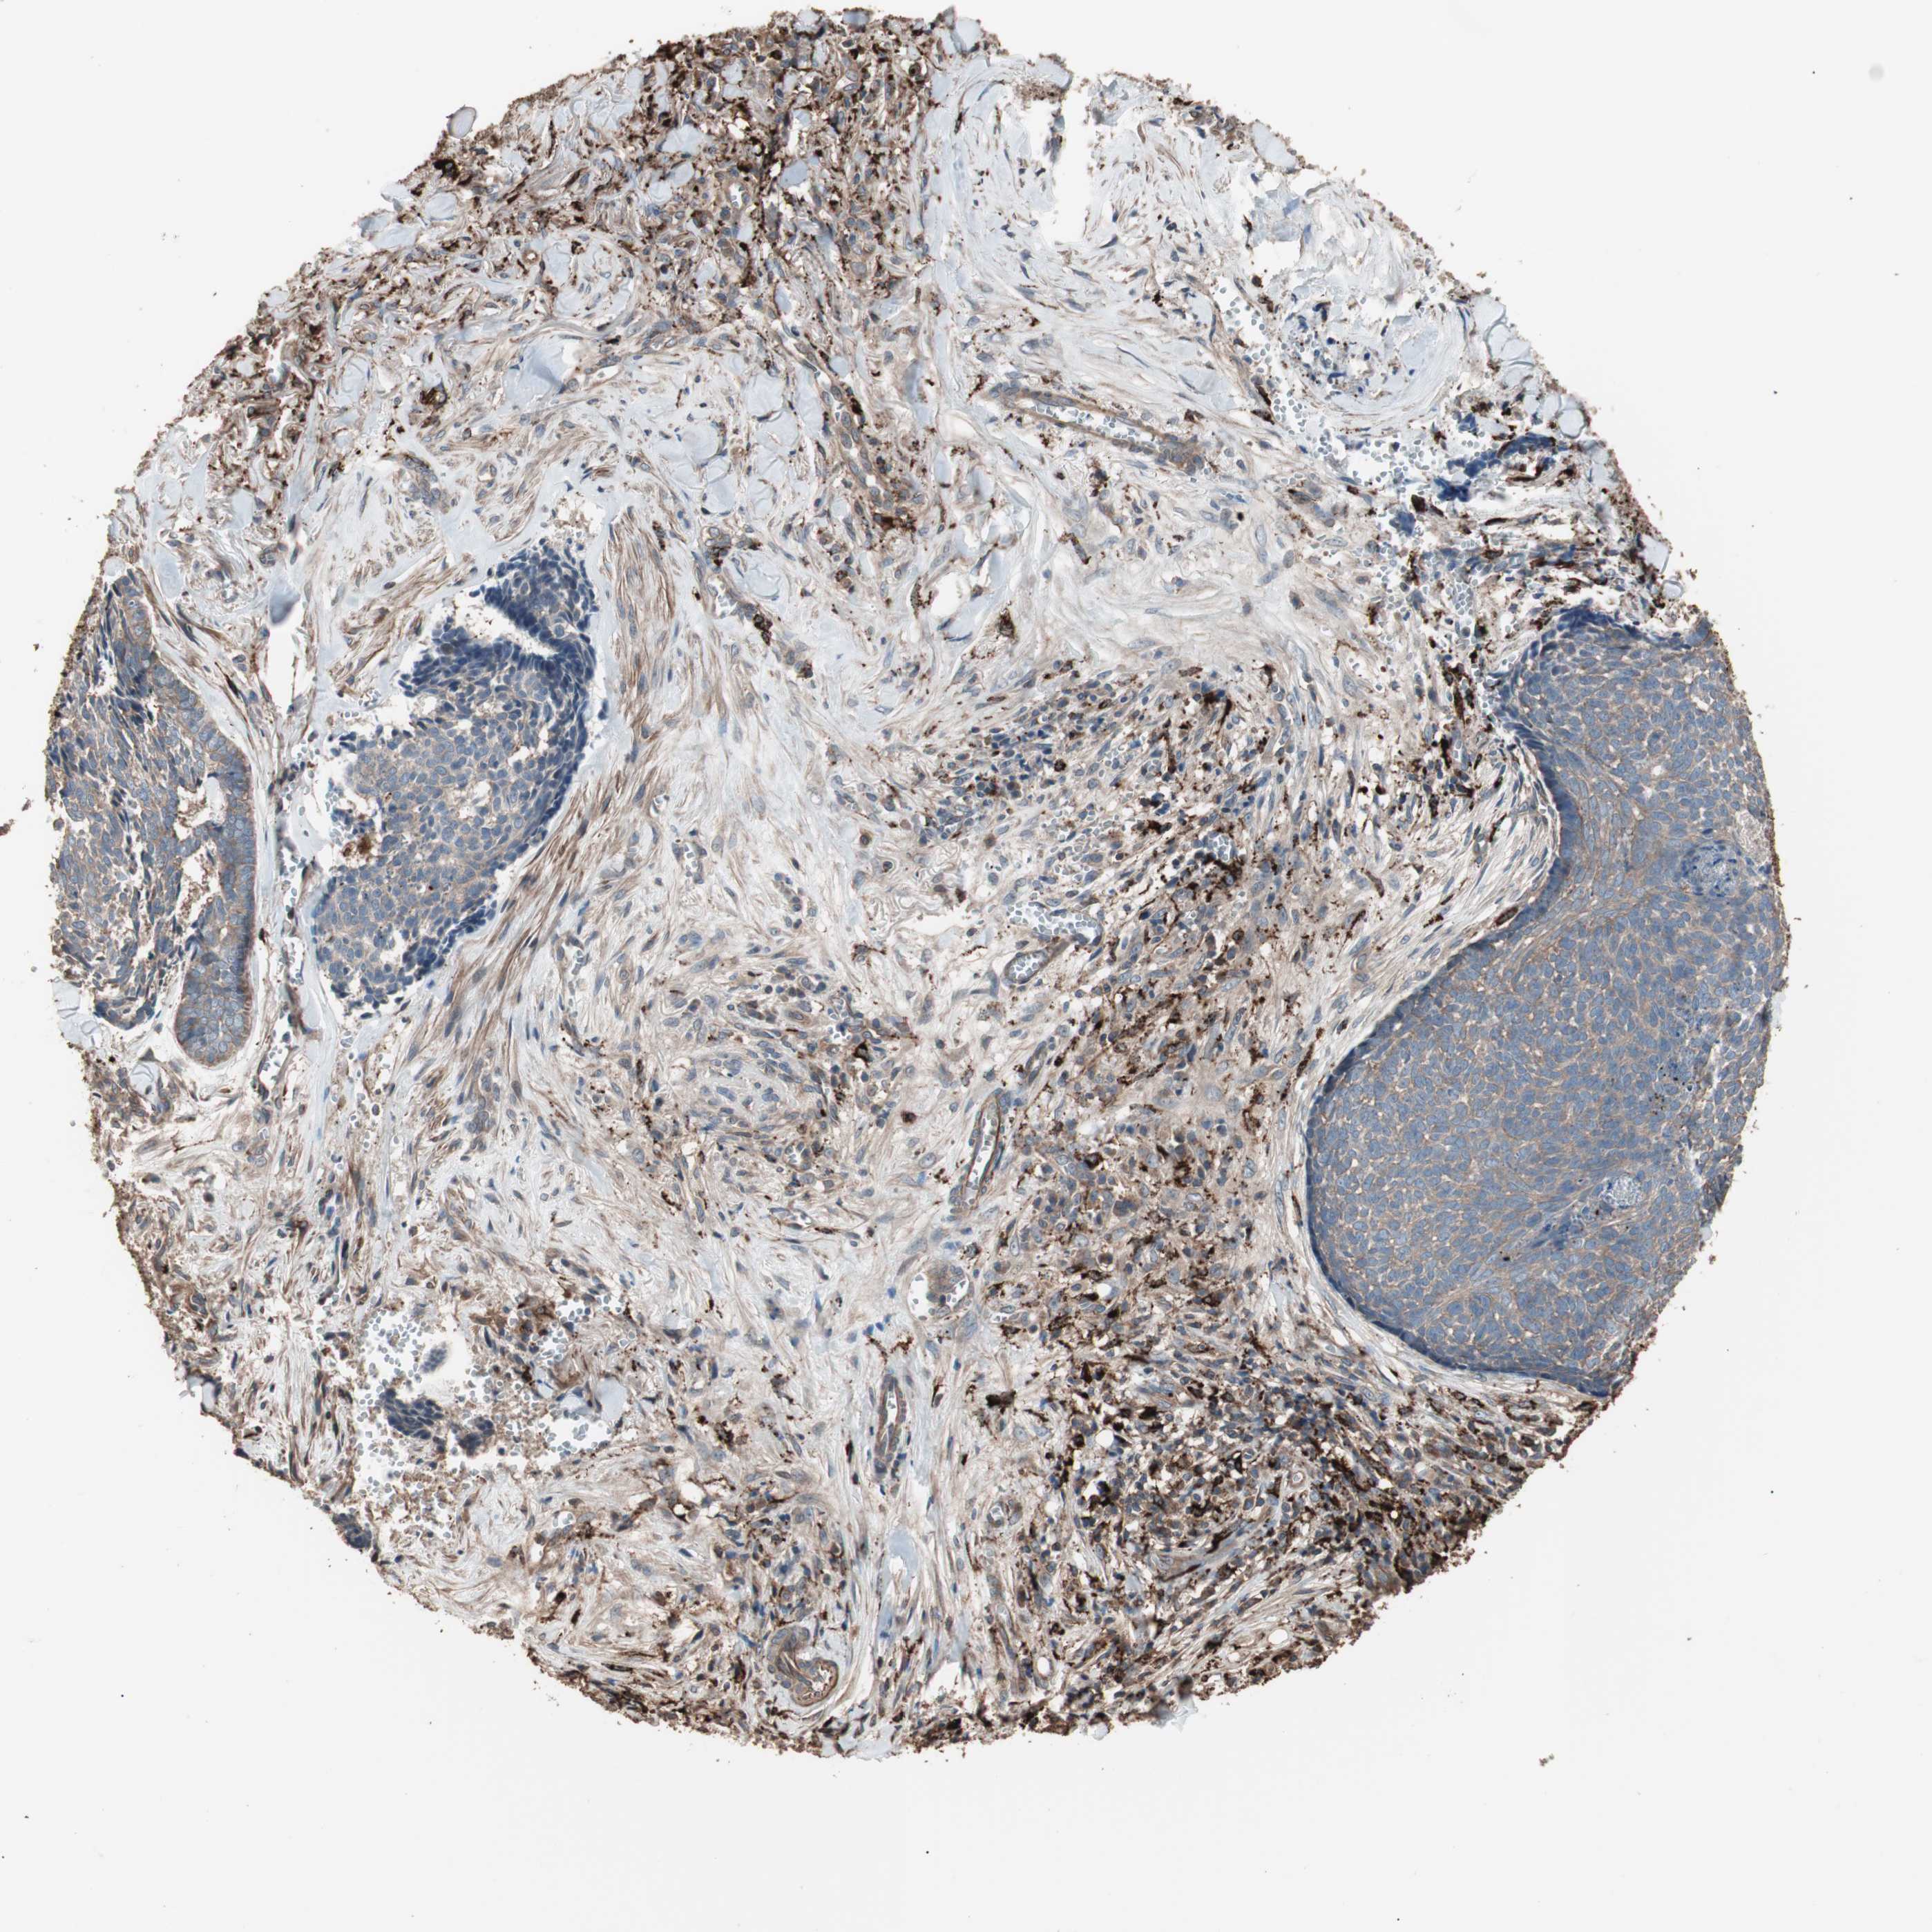

SKIN CANCER - Protein expressioni

A mouse-over function shows sample information and annotation data. Click on an image to view it in a full screen mode. Samples can be filtered based on level of antibody staining by selecting one or several of the following categories: high, medium, low and not detected. The assay and annotation is described here.

Antibody stainingi

Antibody staining in the annotated cell types in the current human tissue is reported as not detected, low, medium, or high, based on conventional immunohistochemistry profiling in selected tissues. This score is based on the combination of the staining intensity and fraction of stained cells.

Each image is clickable and will lead to virtual microscopy that enables deeper exploration of all samples and also displays staining intensity scores, fraction scores and subcellular localization as well as patient and tissue information for each sample.

Antibody HPA006543

Staining

High

Medium

Low

Not detected

Intensity

Strong

Moderate

Weak

Negative

Quantity

>75%

75%-25%

<25%

None

Location

Nuclear

Cytoplasmic/membranous

Cytoplasmic/membranous,nuclear

Squamous cell carcinoma, NOS

Squamous cell carcinoma, metastatic, NOS

Basal cell carcinoma

Papilloma, NOS